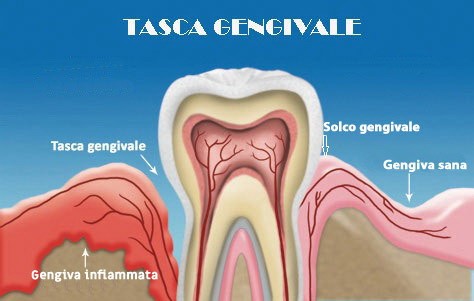

In summary, it is a bacterial pathology which, due to the body’s inflammatory response, leads to the progressive resorption of the alveolar bone (i.e. the bone that keeps the teeth functioning), with retraction of the gums and serious aesthetic and of chewing. The presence of bacteria that accumulate inside the gingival sulcus produces a progressive detachment of the gum with resorption of the bone, causing the formation of a space, called periodontal pocket , which further favors the accumulation and growth of bacteria with worsening of the condition of the tissues .

If the inflammation of the periodontium persists and becomes chronic, the gum detaches from the tooth and the formation of so-called ” gingival pockets ” (dental pockets or gingival pockets).

The pockets will act as a receptacle for subgingival tartar and bacteria. In the strenuous fight between bacterial toxins and immune defenses, the one who loses out is the alveolar bone, which will progressively reabsorb upwards until the tooth is left exposed. As a result, the tooth without surrounding bone will begin to loosen until it falls out , in the absence of appropriate diagnosis and treatment.